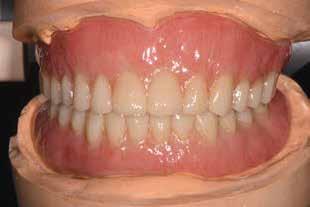

Bevezetés

Az azonnali, implantátumokkal megtámasztott teljes íves fogpótlások jól bevált, és egyre inkább elfogadott kezelési módot képviselnek a teljesen fogatlan betegek rehabilitációjában.1,2 Az ilyen típusú helyreállítások esetében átlagosan 5 éves követési időszakban 98%os túlélési arányról számoltak be.3 Az alsó állkapocs kedvező csontminőségnek és anatómiának köszönhetően az azonnali teljes ívek helyreállítása még nagyobb sikerarányt mutatott.4 A digitális technológiák, mint például a sablonnal végzett implantátumbeültetés és a számítógéppel segített protézistervezés és gyártás, képesek megkönnyíteni a diagnózist, a kezelés megtervezését és jelentősen javítják a sebészeti beavatkozásokat, ezáltal kiszámíthatóbb és hatékonyabb kezelést biztosítanak.5,6 Különösen a bonyolult sebészeti eljárások – mint például a teljes ív rekonstrukciója – jelentős mértékben profitálhatnak ezekből az előnyökből, amelyek csökkenthetik a kezelés idejét és az invazivitást a beteg számára.5,7

A digitális technológiákhoz való hozzáférést az anyagi és időkorlátok akadályozhatják, valamint az ilyen technológiákhoz kapcsolódó meredek tanulási görbe.8,9 A közelmúltban a digitális munkafolyamatok elérhetővé váltak egy kihelyezett szolgáltatás részeként: Smile in a Box (Straumann). Ez segíthet a hagyományos munkafolyamatokat használó szakembereknek, hogy könnyen élvezhessék a digitális technológiák előnyeit anélkül, hogy először le kellene küzdeniük az első hozzáféréssel járó akadályokat. Ez az esettanulmány egy hagyományos teljes fogsor sikeres azonnali átalakítását írja le azonnali teljes ívű restaurációvá a Smile in a Box által biztosított kiszervezett, teljesen digitális munkafolyamat alkalmazásával. A Straumann Pro Arch protokoll alkalmazása a Smile in a Box funkcióval kombinálva lehetővé tette számunkra, hogy könnyen hozzáférhessünk egy teljesen digitális munkafolyamathoz, amely hatékonyan integrálható a hagyományos protetikai munkafolyamatunkba, továbbá rendkívül kielégítő klinikai eredményt biztosít.

Klinikánkon egy teljesen fogatlan, hagyományos akrilát fogpótlással helyreállított 65 éves férfi beteg jelentkezett, aki nem kielégítő alsó fogsorretencióra és az azzal járó problémákra panaszkodott, beleértve a kifejezetten az alsó fogsorához kapcsolódó gyenge beszéd és rágásfunkciót. A klinikai vizsgálat gömbölyűtől a késhegyig terjedő mandibulagerinc formát és megfelelő vertikális, de nem megfelelő vízszintes csontmennyiséget állapított meg, különösen a hátsó területen (1. ábra) 10

témás vagy lokális kockázati tényezőket vagy ellenjavallatokat, amelyek kizárták volna a pácienst az implantációs kezelésből. A különböző kezelési lehetőségekről, azok előnyeiről és korlátairól szóló alapos megbeszélést követően a páciens egy implantátumokon megtámasztott alsó fogsort kombinálva egy új, hagyományos felső teljes kivehető fogpótlást részesített előnyben.

A hagyományos teljes kivehető fogpótlási technikákkal a kezelési stratégia a felső és alsó állcsont kapcsolatának és az okkluzális vertikális dimenzió és a fog helyzetének meghatározását foglalta magában, majd az alsó rögzített restauráció előállításához ezeket használták fel referenciákként (3. ábra) 11